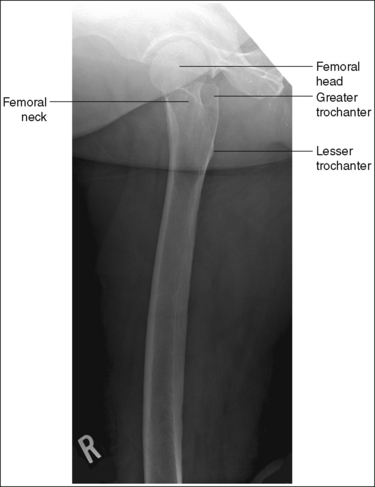

The distal femur demonstrates an AP projection. The medial and lateral femoral epicondyles are in profile, the femoral condyles are symmetrical in shape, and the tibia is superimposed over 0.25 inch (0.6 cm) of the fibular head.

• To obtain an AP distal femoral projection, place the patient in a supine position with the knee fully extended. Internally rotate the leg until the foot is rotated to a 15- to 20-degree angle and an imaginary line drawn between the medial and lateral femoral epicondyles is positioned parallel with the IR (Figures 6-105 and 6-106). This positioning places the medial and lateral femoral epicondyles at equal distances from the IR, as well as medially and laterally in profile, respectively. It also centers the intercondylar eminence within the intercondylar fossa.